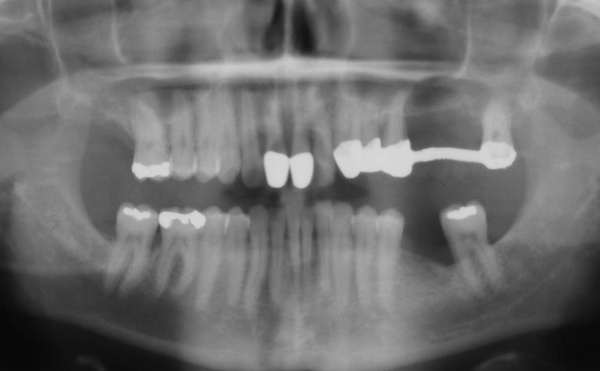

Der Erstbefund zeigte eine generalisiert entzündliche marginale Gingiva mit generalisierter Blutungsneigung bei Sondierung. Die approximalen Sondiertiefen waren durchgehend erhöht und betrugen im Molarenbereich bis zu 12 mm (s. Abb. 4). Es lagen multiple Zahnlockerungen vor, eine Zahnlockerung des Grades II zeigte sich an den Zähnen 11, 25, 26, 38, 37, 47; Grad III am Zahn 24. Harte Beläge in der Unterkieferfront, generalisiert weiche Beläge (API 62 %). Wurzelkaries an 24. Suffiziente Brückenversorgung im I. Quadranten. Die Panoramaschichtaufnahme von Juni 1998 (s. Abb. 4) zeigt einen generalisierten horizontalen Knochenabbau mit vertikalen Einbrüchen in regio 17, 25, 37 und 47. Interradikuläre Aufhellungen im Sinne einer Furkationsbeteiligung an 17, 26, 38, 37 und 47. Via falsa an 24.

Der Erstbefund vom 20.08.1998 zeigte eine lokalisiert entzündliche marginale Gingiva mit Blutungsneigung auf Sondierung (SBI 32 %) vorrangig in regio 17, 11, 21, 24, 27, 36, 37, 41, 46. Austritt von Pus aus der Tasche an 22. Die Sondiertiefen waren durchweg erhöht, an einzelnen Parodontien konnten bis zu 12 mm sondiert werden (s. Abb. 12). Generalisiert weiche Beläge (API 46 %), harte Beläge in der UK-Front. An 41 singuläre parodontale Rezession und Zahnlockerung des Grades II, hier auch sehr schmale keratinisierte Gingiva. Mobilitätstest und Blanchingtest positiv. Der Röntgenbefund der Panoramaschichtaufnahme vom 11.08.1999 (s. Abb. 13) zeigt einen generalisierten horizontalen Knochenabbau mit vertikalen Einbrüchen in regio 17, 24, 25, 26, 36, 41 und 47. Wurzelfüllung an 36. Konkremente sichtbar. 18 elongiert. 38 und 48 halbretiniert mit Aufhellung distal.